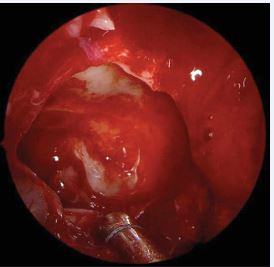

Reboot technique: step by step Reboot surgery is the technique that aims to completely remove the thickened and inflamed sinus mucosa, including all polyp formation in all affected sinuses, mainly involving the ethmoid and maxillary sinuses bilaterally, as well as part of the mucosa of the sphenoid and frontal sinuses. Furthermore, in case of edema or polyp formation on the middle turbinates, they must be adequately resected. The upper turbinates may also show polyp growth, which must be removed; however, the turbinates should be preserved as much as possible to maintain olfactory function. Additionally, the frontal sinuses may be involved, and a simple resection of the medial part of the frontal mucosa may be necessary, if sufficient space remains to maintain the opening long-term. Otherwise, a resection of the frontal sinus floor anteriorly and laterally may be indicated to maintain access. In cases of difficult access to the frontal sinus and/or extended frontal disease, it may be necessary to combine the Reboot technique with the DRAF III approach (full Reboot), to ensure access to the sinus and removal of the massively affected frontal mucosa.The surgeon must begin the procedure through a wide antrostomy and complete removal of the maxillary sinus mucosa, including the alveolar recess, using 30° and 70° endoscopes (Figures 1, 2 and 3).

https://www.jscimedcentral.com/public/assets/images/uploads/image-1764067750-1.JPG

Figure 1 Reboot surgery approach. Use of 360o rotating antrum forceps in the maxillary sinus, right side.